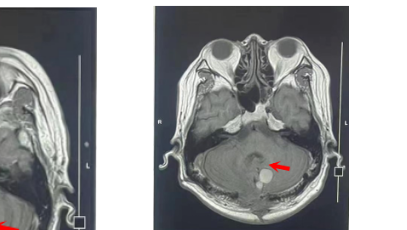

我科具备了与神经外科专业配套的大型设备和手术器械,有1.5T核磁共振(MRI)、64排螺旋CT、DSA造影机、高压氧舱、手术显微镜(蔡司)、神经外科手术头架(Mayfield)、重症监护病房(ICU)和康复医学机器人等设备等,为神经外科病人的诊断、手术治疗及康复治疗提供了全方位一体化的治疗保障。

1.5T核磁